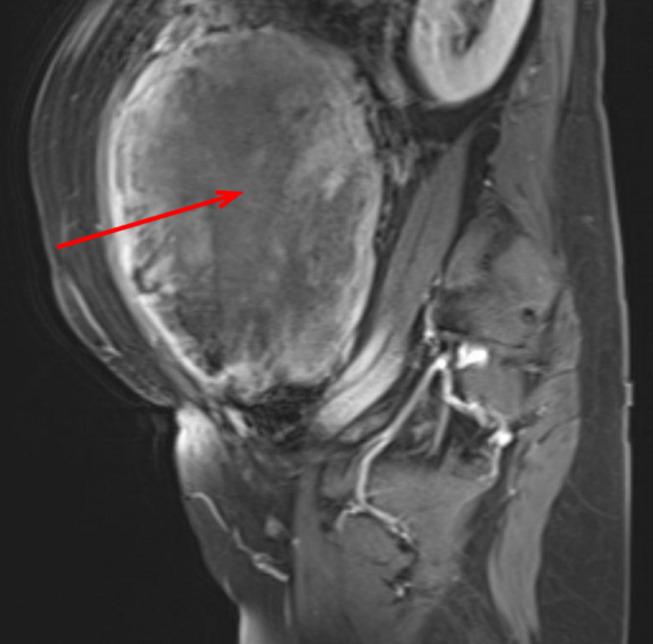

伴有奇异核的平滑肌瘤:最新进展

Leiomyoma with Bizarre Nuclei: A Current Update.

Leiomyoma with bizarre nuclei (LBN), also known as symplastic leiomyoma, is a histological subtype of benign leiomyoma with bizarre cells and nuclear atypia. Differentiating LBN from other benign leiomyoma subtypes, uterine smooth muscle tumors of uncertain malignant potential (STUMP), or leiomyosarcoma (LMS) can be diagnostically challenging owing to overlapping features in clinical presentation and pathologic morphological analysis. The difficulty of distinguishing LBN from other lesions, especially from LMS, and the potential of LBN for subsequent malignant transformation make LBN an important topic of research. Herein, we review the definition, diagnosis, treatment, and prognosis of LBN. Histopathological examination is essential for distinguishing LBN from other diseases. Pathology sampling and morphological examination remain the key to diagnosis. The newly established ancillary immunohistochemical (IHC) and molecular genetic analysis can be useful tools for differential diagnosis. Furthermore, serum biomarkers and imaging examination may also be useful diagnostic tools. Attention should be paid to the differentiation between LBN and LMS because morphological diagnosis may still be challenging in some cases. Some IHC markers of LBN have been identified, which may be helpful for differential diagnosis. Furthermore, the use of IHC panels as diagnostic markers may be advocated. Molecular genetic studies suggest that some genes can aid with the differential diagnosis between LBN and LMS. However, increasing evidence support the idea that LBN and LMS are molecularly related, indicating that LBN may represent a potentially malignant stage of precancerous progression. At present, conservative treatment is recommended for primary LBN, especially for patients desiring to retain fertility, but close follow-up with imaging examinations is required.

摘要

Uterine fibroid-like tumors: spectrum of MR imaging findings and their differential diagnosis.子宫平滑肌瘤样肿瘤:磁共振成像表现谱及其鉴别诊断

Abdom Radiol (NY). 2022 Jun;47(6):2197-2208. doi: 10.1007/s00261-022-03431-6. Epub 2022 Mar 26.